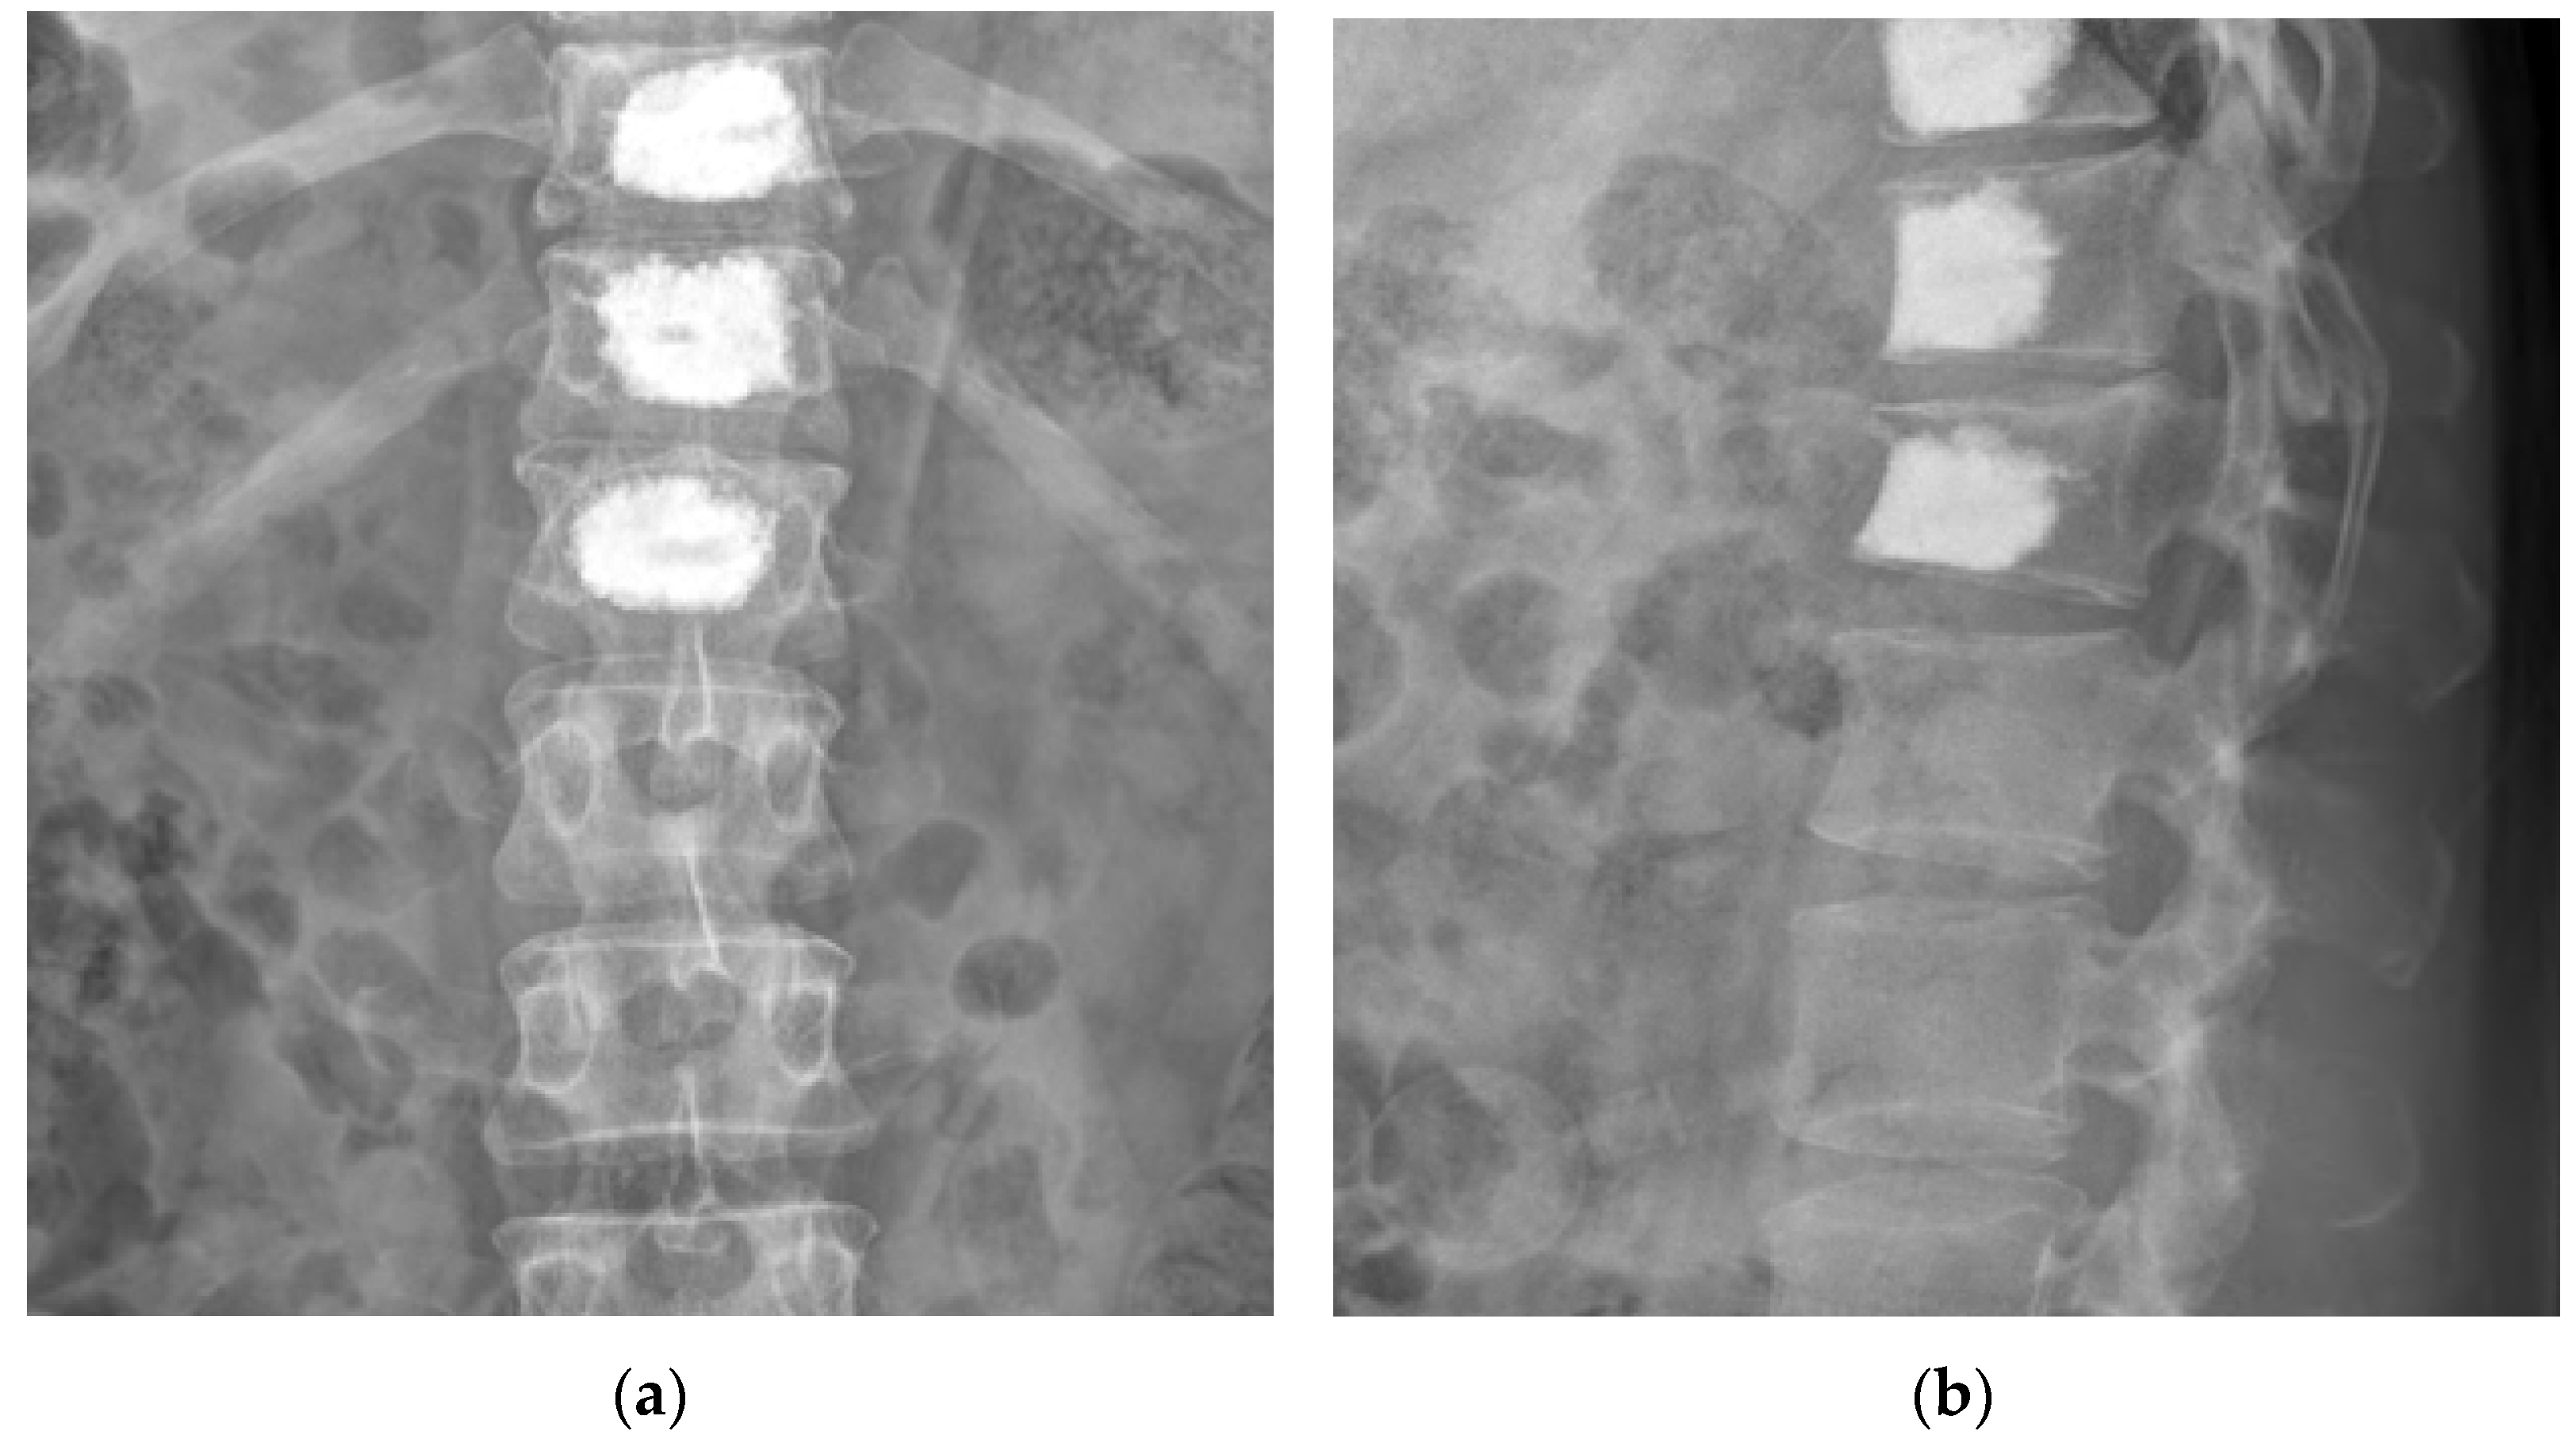

2. Case Presentation